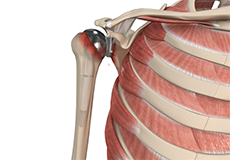

Total shoulder replacement is the replacement of the head of the humerus (upper arm bone) and the glenoid cavity (cavity of the shoulder blade) into which the humerus fits, with artificial prostheses to relieve pain, swelling, and stiffness caused due to damage of cartilage at the articulating surfaces.